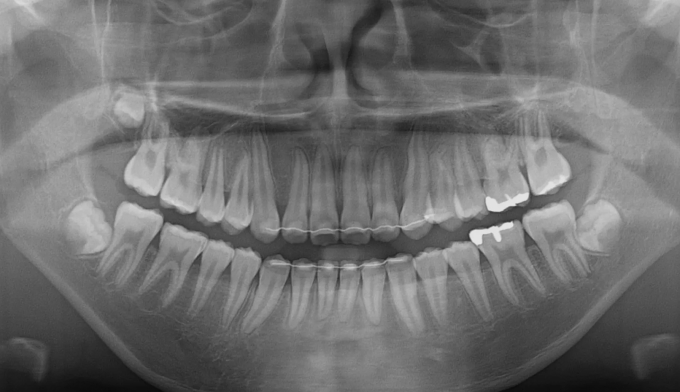

유치를 제때 뽑아주지 못하면 치아 맹출 순서가 뒤죽박죽이 되면 잇몸 안에서 맹출하지 못하게 됩니다.

본 케이스처럼 아예 치아의 각도가 누워버린 경우에는 억지로 교정장치를 부착하여 치아를 제 위치로 당겨주어야 합니다.

잇몸의 일부를 절개하여 교정장치 부착후 치아를 견인하였고 총 치료기간은 16개월입니다.

잠깐의 고생이지만 살려놓은 치아는 평생쓸 수 있는 자산입니다.